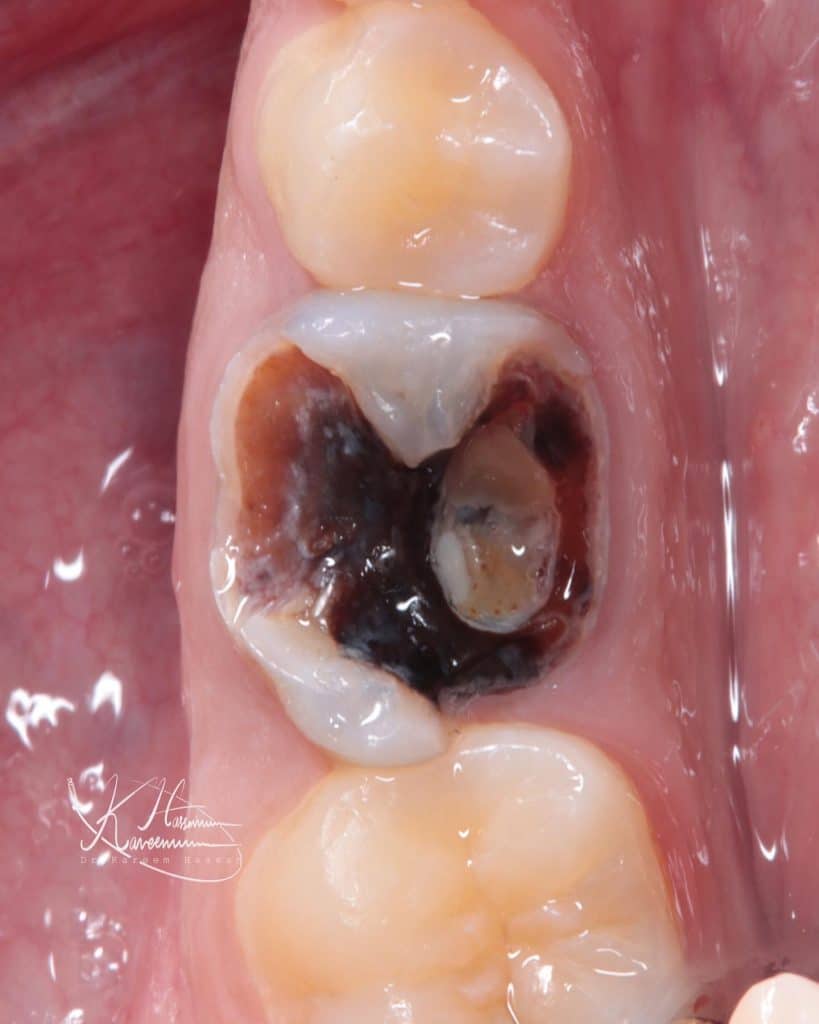

Caries Detecting Dye staining the denatured dentin is the corner stone for every minimally invasive adhesive restoration as it shows you what should be remove and what should be kept following the right protocol (Alleman & Magne 2012).

Initial situation

CDD